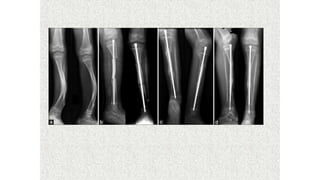

This document discusses a disease and its investigation and management. It begins by introducing Dr. Aniket Wankhede from MGIMS Sevagram and asks what the disease is. It then asks how the disease happens and discusses its causes. Next it asks how the disease appears on x-rays and describes symptoms some people experience living with it. Finally, it asks how the disease will be investigated and managed.